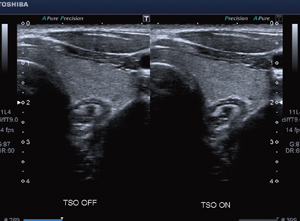

High Density Beamformingとは,高画質を実現する新画像エンジンである。生体特性(音速など)のバラツキによる方位分解能の劣化を補正し改善する“TSO(Tissue Specific Optimization)”(図2,3)をはじめ,空間/周波数コンパウンド技術により空間分解能を向上させる“ApliPure+”,組織の連続性を高め,コントラスト分解能を向上させる“Precision Imaging”により高画質を実現している。また,腹部エコーにおいて,従来の画質を保ちつつ従来の2倍以上のフレームレートを実現し,小病変の検出能の向上に期待されている。

![]() 図2 ビームの絞りを補正し方位分解能を向上させるTSO |

![]() 図3 TSOの効果 |